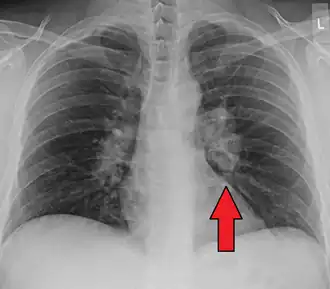

Chest radiograph changes are divided into four stages:[104]

- bihilar lymphadenopathy

- bihilar lymphadenopathy and reticulonodular infiltrates

- bilateral pulmonary infiltrates

- fibrocystic sarcoidosis typically with upward hilar retraction, cystic and bullous changes

Although people with stage 1 radiographs tend to have the acute or subacute, reversible form of the disease, those with stages 2 and 3 often have the chronic, progressive disease; these patterns do not represent consecutive "stages" of sarcoidosis. Thus, except for epidemiologic purposes, this categorization is mostly of historic interest.[28]

-

Hilar adenopathy especially on the person's left (AP CXR) -

Hilar adenopathy especially on the person's left (lateral CXR) -

Hilar adenopathy especially on the person's left (coronal CT) -

Hilar adenopathy especially on the person's left (transverse CT)